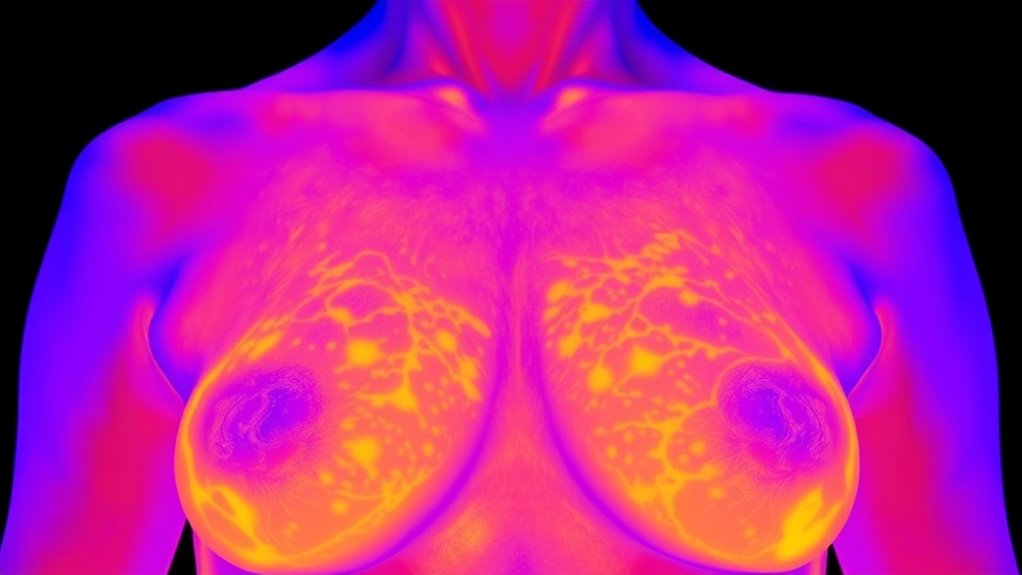

Die Thermografie funktioniert durch die Verwendung von Infrarotkameras, um Oberflächentemperaturveränderungen auf der Haut der Brust zu erkennen. Diese Wärmebilder zeigen Bereiche mit vermehrtem Blutfluss oder erhöhtem Stoffwechsel, was auf zugrunde liegende Probleme hindeuten kann. Da sie jedoch nur die Oberflächenwärme misst, kann die Thermografie die innere Struktur des Brustgewebes nicht sichtbar machen. Diese Einschränkung bedeutet, dass sie keine kleinen Tumore oder detaillierte Anomalien im Inneren der Brust erkennen kann. Zudem können Wärmemuster durch nicht-krebsartige Faktoren wie Entzündungen, Infektionen, hormonelle Veränderungen oder Umwelteinflüsse beeinflusst werden, was zu falsch positiven oder falschen negativen Ergebnissen führen kann. Die Thermografie liefert keine anatomoischen Bilder oder genaue Lokalisierungen von Anomalien, was sie bei der Diagnose von Brustkrebs weniger zuverlässig macht. Ihr oberflächenorientierter Ansatz beschränkt ihre Fähigkeit, durch genauere strukturelle Bildgebung wie Mammographie ersetzt zu werden.

Vergleich der diagnostischen Genauigkeit von Thermografie und Mammographie

Beim Vergleich der diagnostischen Genauigkeit von Thermografie und Mammographie zeigt sich, dass die Mammographie deutlich zuverlässiger ist. Die Empfindlichkeit der Mammographie liegt bei etwa 80,5 % bis über 90 %, was sie effektiver bei der Erkennung von Brustanomalien, einschließlich kleiner Tumoren, macht. Im Gegensatz dazu variiert die Empfindlichkeit der Thermografie zwischen 42 % und 81,6 %, wobei sie häufig Krebs übersieht oder falsch positive Ergebnisse liefert. Die Mammographie weist auch eine höhere Gesamtgenauigkeit von etwa 77 % auf, während die Genauigkeit der Thermografie bei etwa 70 % liegt. Da die Mammographie direkt das Brustgewebe abbildet, liefert sie entscheidende strukturelle Informationen, die für die Diagnose unerlässlich sind. Thermografie, die Temperaturveränderungen an der Oberfläche erkennt, kann versteckte Tumoren nicht zuverlässig identifizieren oder zwischen benignen und malignen Zuständen unterscheiden. Diese geringere diagnostische Präzision macht die Mammographie zur beweisgestützten, bevorzugten Methode für die Brustkrebsfrüherkennung.